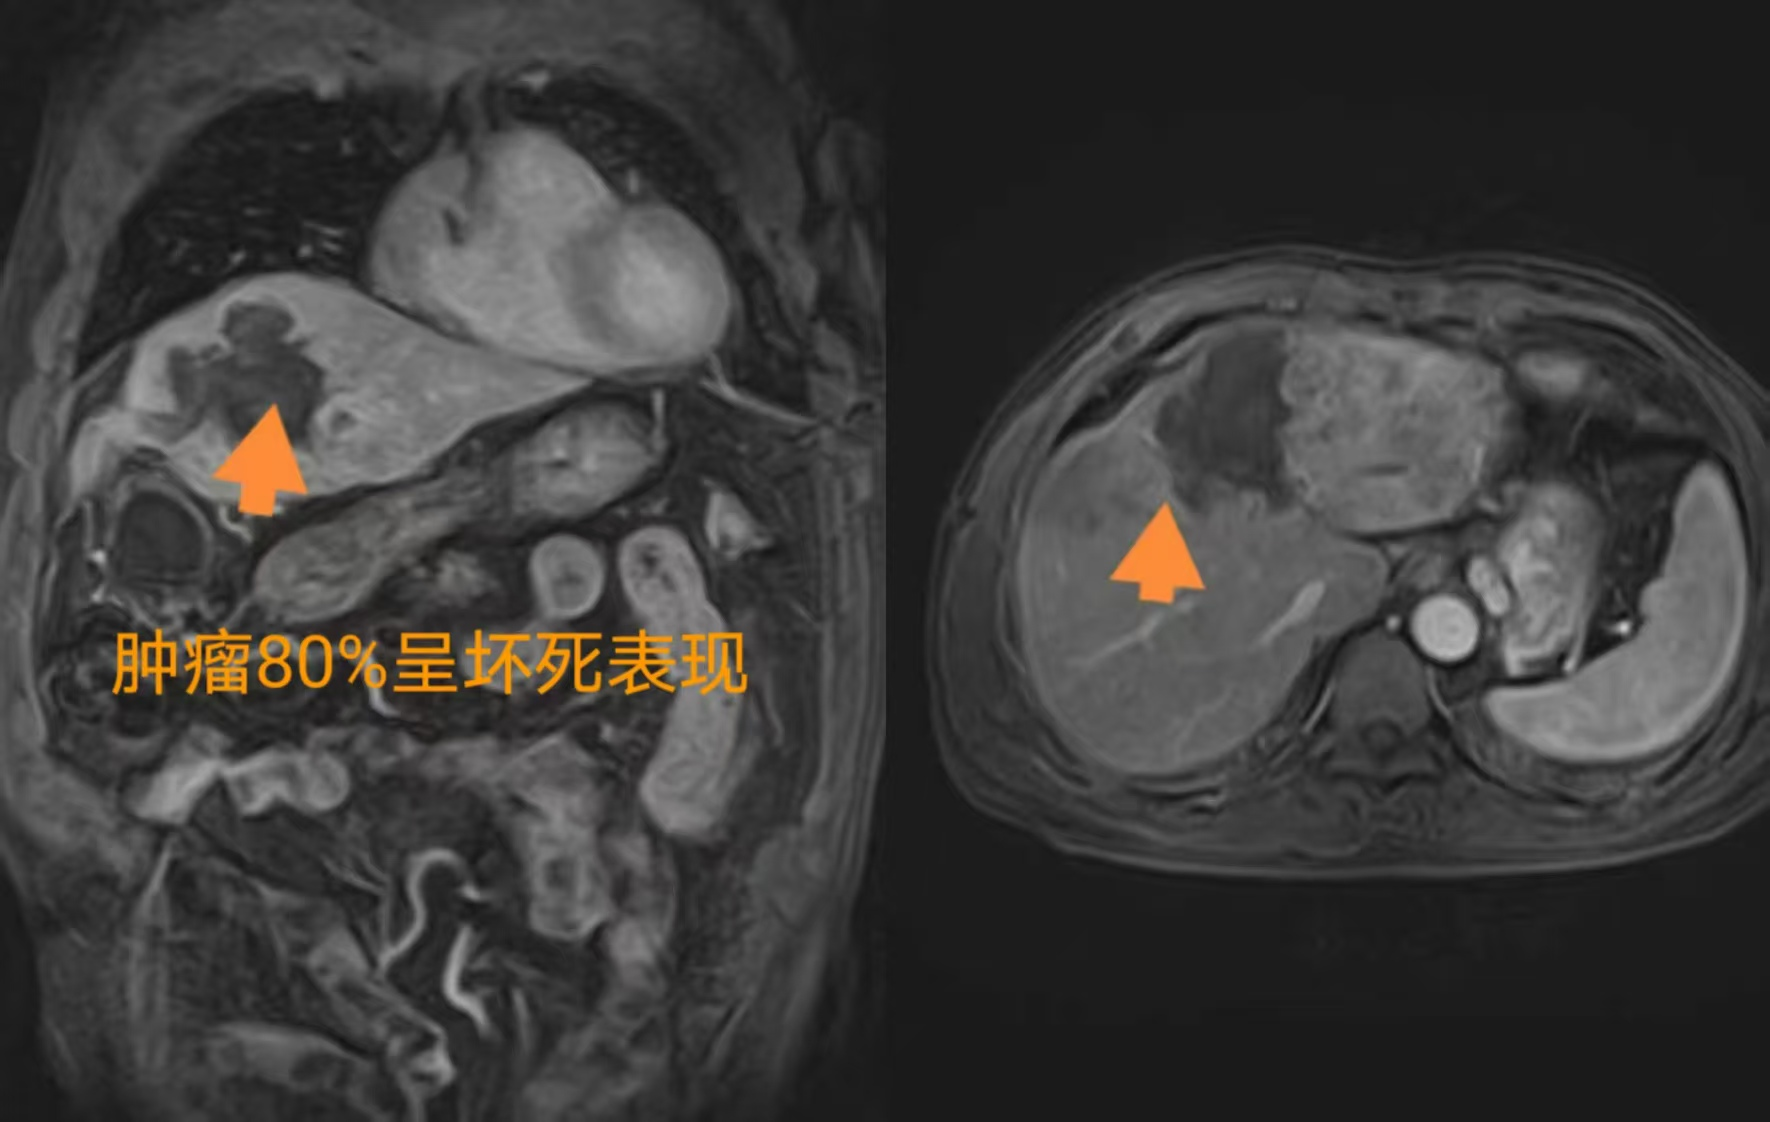

随后,进一步明确肝左叶肿瘤行组织穿刺明确性质,病理报告及免疫组化报告提示:中分化肝细胞癌。磁共振显示肝左叶肿瘤大小约9.0*7.8*6.6cm,且门脉主干、左右支及左支次级分支、肠系膜上静脉腔内广泛索条状、片结状,提示门脉内血栓伴癌栓。结合肿瘤恶性,肿瘤较大,且合并多处栓子,因此需要多疗程治疗来尽可能的控制病情发展和根据实际病情变化情况来调整治疗方案。(如下图)

2025年2月16日杨先生如期来到成都聚焦超声医院,进行第二次疗程治疗。2025年3月21日于当地医院复查:肝肾功未见明显异常,肿瘤标志物正常范围,磁共振显示肿瘤和门脉癌栓呈消融坏死表现,但考虑到肿瘤浸润性生长,建议再次对肿瘤边缘部分行巩固消融治疗,扩大消融范围,更好的控制肿瘤,2025年4月27日再次来院进行聚焦超声消融治疗。(下图为2025年3月21日复查磁共振)